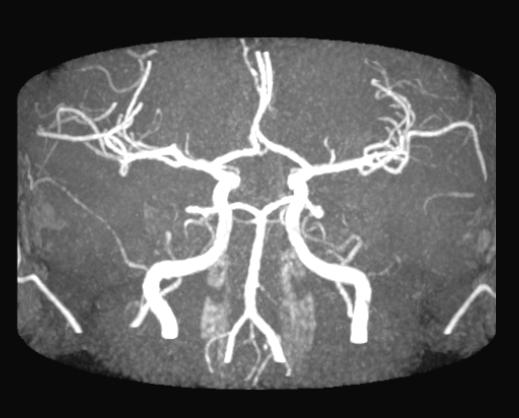

De cirkel van Willis is een vaatstructuur die een enorm belangrijke rol speelt in het waarborgen van de arteriële perfusie naar het gehele brein. Deze structuur ligt aan de basis van het brein, anterieur van de hersenstam. De ‘cirkel’ verwijst naar de anastomoses (verbindingen) die binnen de cirkel worden gemaakt; daar komen we zo op. Voor nu is het goed om erbij stil te staan dat we de meest gangbare anatomie bespreken. Er bestaat variatie tussen mensen in hoe compleet de cirkel van Willis is. Deze anatomische variatie is een belangrijke determinant van de gevolgen van een occlusie in één van de vaten. Middels een CT-scan met arterieel contrast, of met een MR-A of met katheterangiografie kan de anatomie van de cirkel van Willis worden beoordeeld (zie bijv. de CT-scanreconstructie hiernaast).